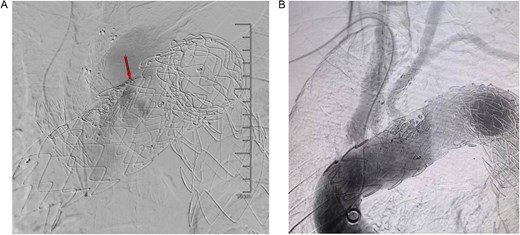

On March 1, 2024, the patient was readmitted for recurrent blood in phlegm. CTA revealed a type IV endoleak caused by membrane rupture. Angiography identified the endoleak at the stent graft junction (Fig. 8A). Controllable embolization coils were deployed to embolize the rupture. Post-surgery, symptoms disappeared (Fig. 8B).

(A) On March 1, 2024, the angiography showed endoleak (marked by arrows) at overlapping part of stent graft. (B) Dense embolization was performed on the residual breach of the stent graft membrane.